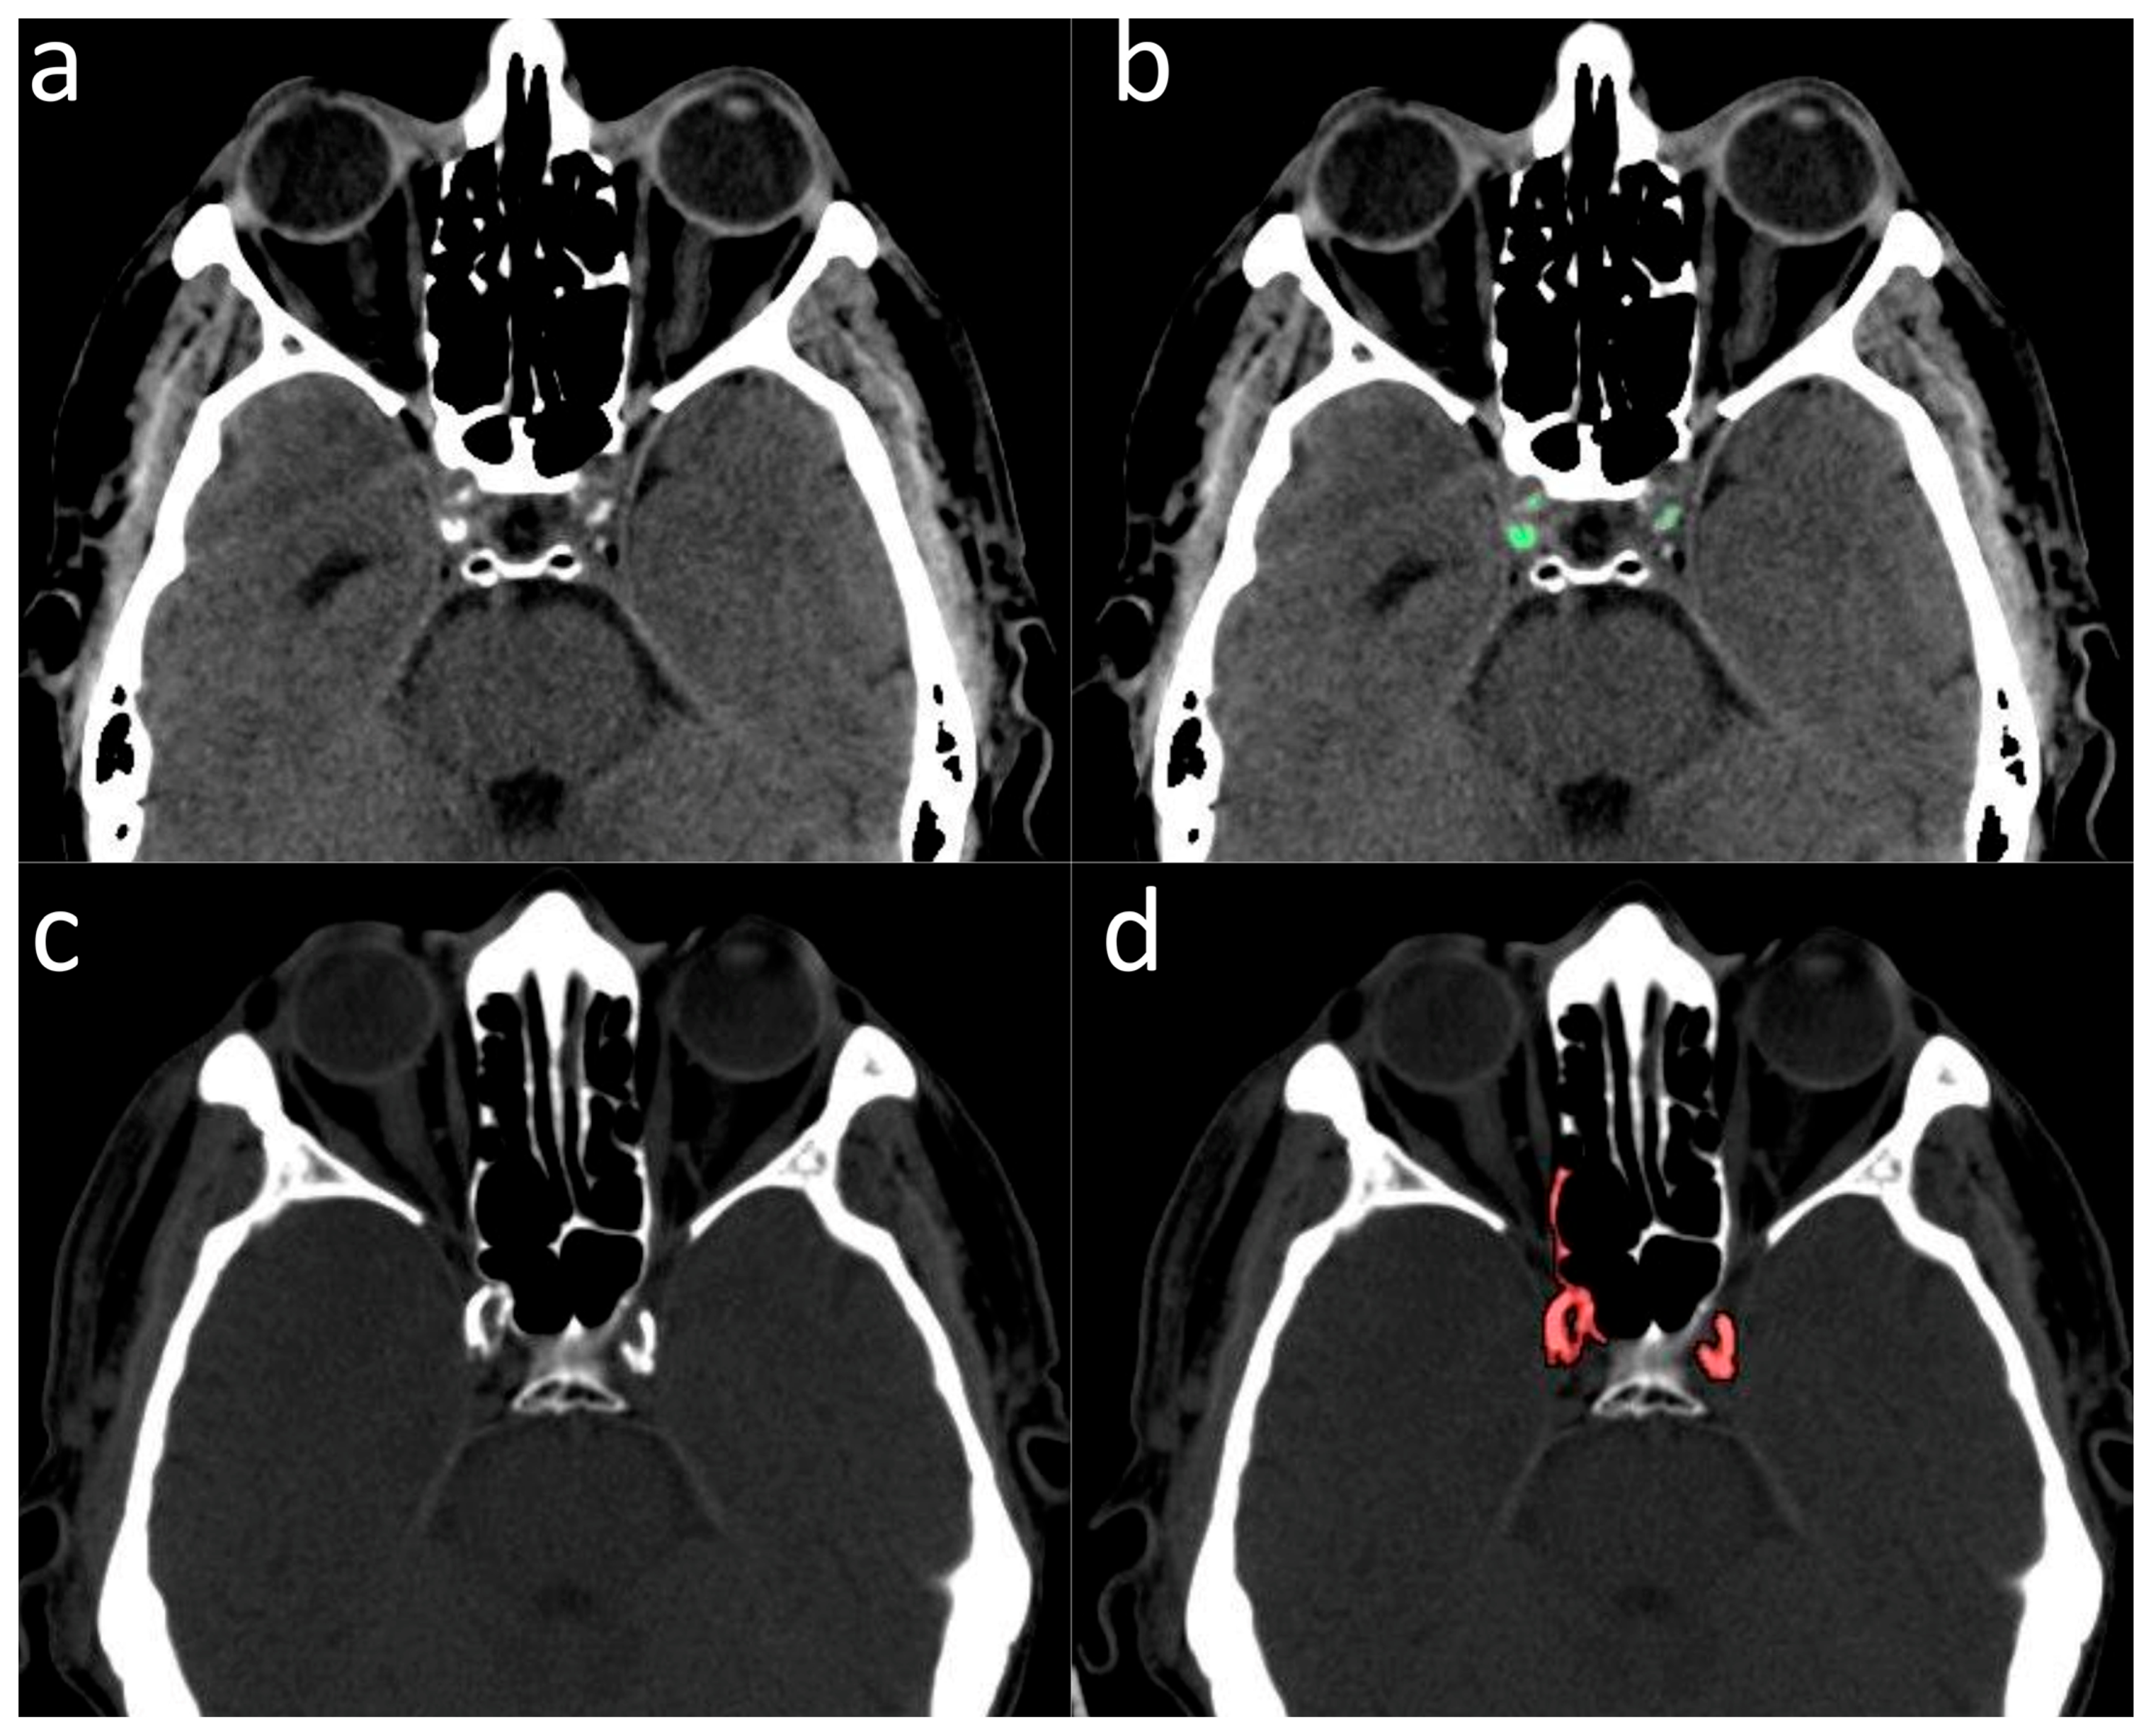

2.2. Validation of ICA Calcium Score as Surrogate Marker of CACs